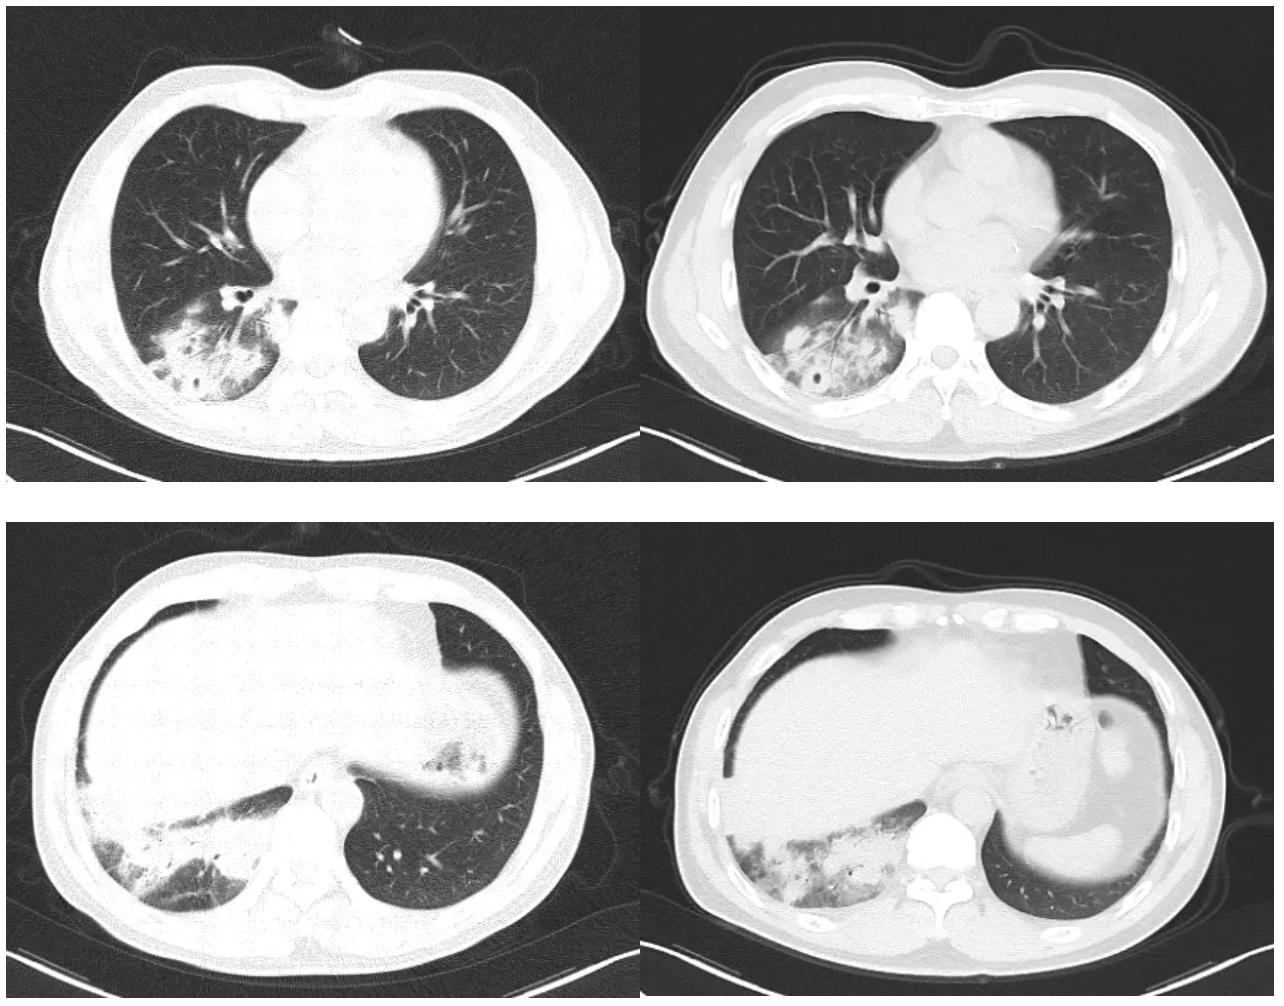

在此阶段,我们修正诊断后,加用了氟康唑400mg/d抗隐球菌治疗。治疗3天后患者咳嗽、胸闷症状出现明显缓解,治疗8天后复查胸部CT示右肺下叶炎症较前稍减轻,右侧少量胸腔积液较前减少(图5)。

图5:氟康唑治疗8天后胸部CT对比,左侧为治疗前,右侧为治疗后